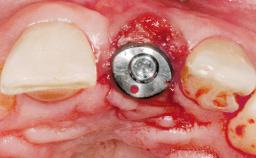

Immediate Flapless Placement of an Implant in a Maxillary Left Central Incisor Site

A 42-year-old female patient was referred to our clinic at the School of Dentistry of the University of São Paulo in November 2004, presenting a deficient restoration in the upper left central incisor. The clinical examination revealed no gingival retraction or any signs of gingival inflammation and, therefore, previous periodontal treatment was not considered. The patient presented a high lip line at full smile and a thin tissue biotype. This combination characterized a high-risk situation from an anatomic point of view, which required careful preoperative planning and cautious surgical execution.

Placement Protocol Immediate implant placement

Tooth Site Maxillary incisor or canine

Socket Morphology Single-root socket

Socket Integrity Sufficient, with intact bone walls

Loading Protocol Immediate

Retention Screw-retained Screw-retained